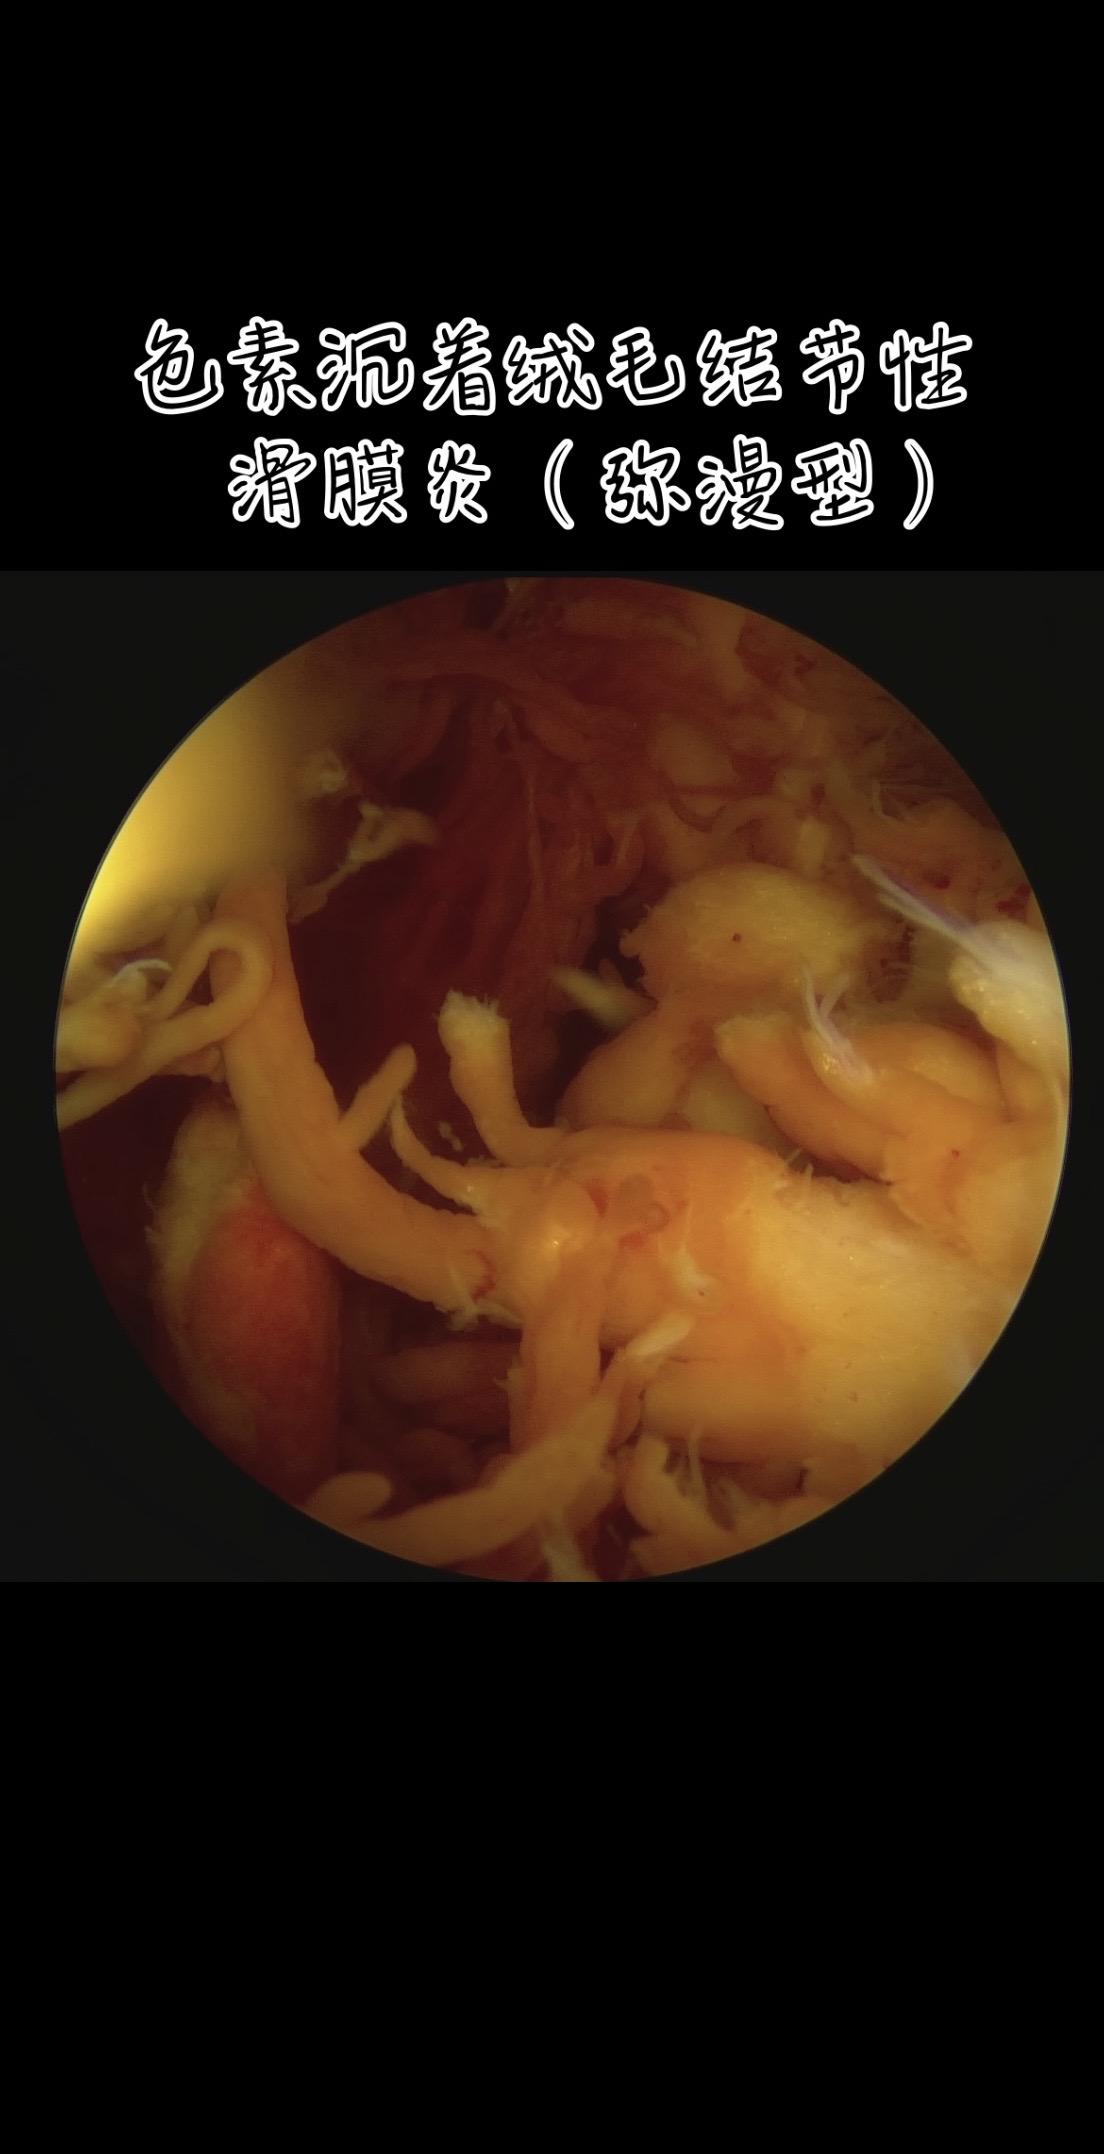

色素沉着绒毛结节性滑膜炎。膝关节反复肿,弥漫型色绒,(PVNS)